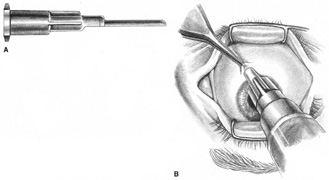

Atkinson16 discussed supplementing incomplete akinesia by injecting 0.5 to 1.0 mL of anesthetic solution 3 cm back along a rectus muscle, if it was still active after retrobulbar block. He grasped a horizontal rectus muscle with forceps and rotated the eye away from the needle, or placed a muscle hook under the eyelid and separated it from a vertical rectus muscle before injection.16 Because the rectus muscles measure 40 to 42 mm in length without their tendons, which in turn may vary from 3.7 mm for the medial rectus to 8.8 mm for the lateral, Atkinson's injection was administered 14 to 21 mm anterior to the origin of the muscle. This would place it anterior to the insertion of the oculomotor branch innervating the muscle. Because akinesia can be achieved with this technique, the anesthetic must be diffused within the muscle, blocking distal branches of the oculomotor divisions at their most distal myoneural junctions. However, these injections may produce myotoxicity with prolonged muscle paresis.53,54

Because permanent extraocular muscle damage is more a product of intramuscular or intraneural injection than of the concentration of anesthetic injected,48,55 a less traumatic delivery of anesthetic can be used around the extraocular muscles to achieve akinesia without risking either myotoxicity or needle trauma to the adjacent optic nerve and orbital vessels. Using the sub-Tenon's space for this delivery allows for such atraumatic akinesia.